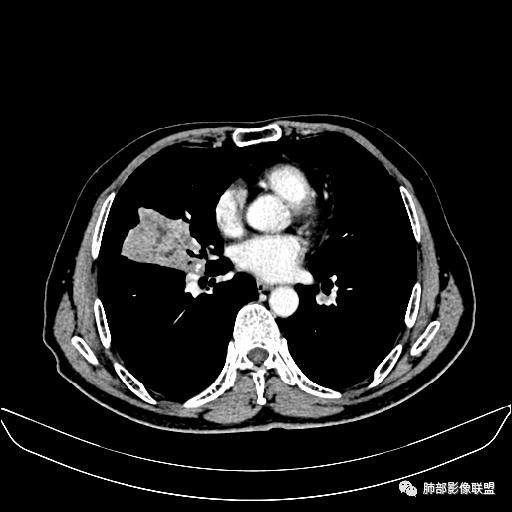

住院4天后行胸部增强CT

老年男性,因“咳嗽咳痰1月余。”入院。病程中咳嗽咳痰,咳黄白痰,间断咯少许鲜红色痰血。PPD阳性。胸CT:右肺中叶外侧段支气管管腔阻塞,大片实性病变,病灶边缘光滑,部分边缘膨隆,可见分叶,肺门及纵隔可见肿大淋巴结,并可见钙化。增强可见病灶明显强化,而且延迟强化明显,病灶内多发低密度区,内见血管影,血管变细、部分血管破坏。考虑恶性病变可能性大,鉴别慢性肉芽肿性病变。

胸CT:跨叶大肿块,主体在中叶,右中叶外侧段支气管阻塞,病灶部分边缘膨隆,可见分叶,部分边缘平直,肺门及纵隔可见肿大淋巴结。增强病灶不均匀强化,延迟强化明显,病灶内多发低密度区,内见血管飘浮,部分血管变细、模糊。考虑:恶性病变可能性大,大细胞?淋巴瘤?鉴别慢性肉芽肿性病变。

右肺中叶软组织肿块,外围向内生长,叶间胸膜向前内移位,肿块近肺门侧跨叶,中叶外侧段支气管截断,密度不均匀,双侧肺门及隆突下见肿大淋巴结,增强后呈中度不均质强化,肺动脉供血,多发坏死区,边界尚清,坏死区域内见结构,结合病史考虑恶性,鉴别诊断1结核,爬行征是沿支气管树分布,外宽,内窄,周围有卫星灶,内气管狭窄后扩张,此例沿叶间胸膜长轴分布,气管有截断,不典型。2炎性肉芽肿,符合的地方下方层面增强后延迟性轻度环形强化,不符临床无发热等急性感染病史,实验室指标不符,病灶周围渗出及慢性炎性改变有,不明显。